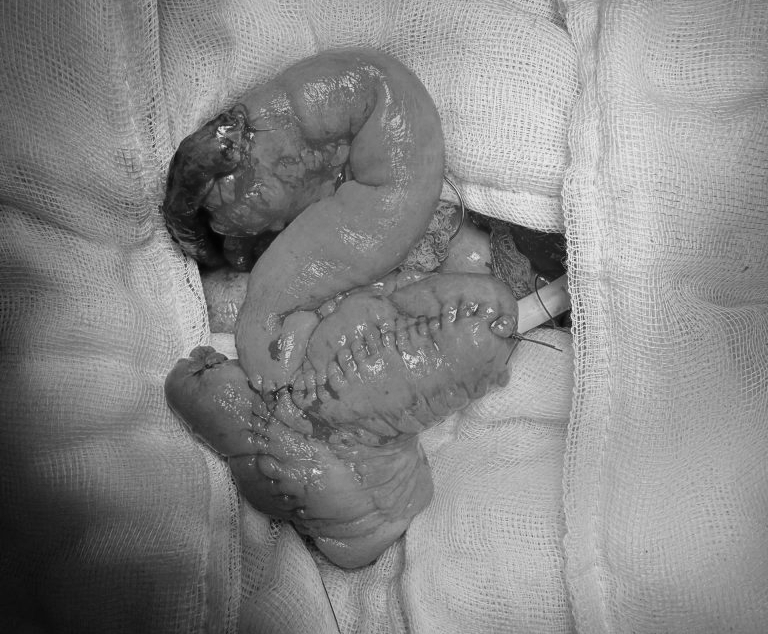

Hình ảnh bàng quang được tái tạo từ ruột non. Ảnh: BVCC

ThS. BS. Lâm Văn Chương – Khoa Ngoại Tiết Niệu cho biết: “Trong quá trình mổ, ê-kíp chúng tôi đã cắt bỏ bàng quang chứa khối u xâm lấn và tạo hình bàng quang bằng một đoạn ruột non theo phương pháp Studer. Đây là một trong những kỹ thuật phức tạp và tiên tiến nhất trong niệu khoa.

Với kỹ thuật này, các bác sĩ đã khéo léo sử dụng một phần ruột của chính bệnh nhân để tạo thành một bàng quang mới và nối nó trở lại vào đường dẫn tiểu tự nhiên giúp người bệnh có thể đi tiểu theo ngả tự nhiên mà không cần phải mang túi chứa nước tiểu bên hông vĩnh viễn.

Kết quả giải phẫu bệnh sau mổ cho thấy diện cắt không còn tế bào ung thư. Điều này có nghĩa là khối u đã được lấy trọn, giải quyết tận gốc nguyên nhân bệnh và mang lại cho ông N. cơ hội chữa khỏi bệnh.”